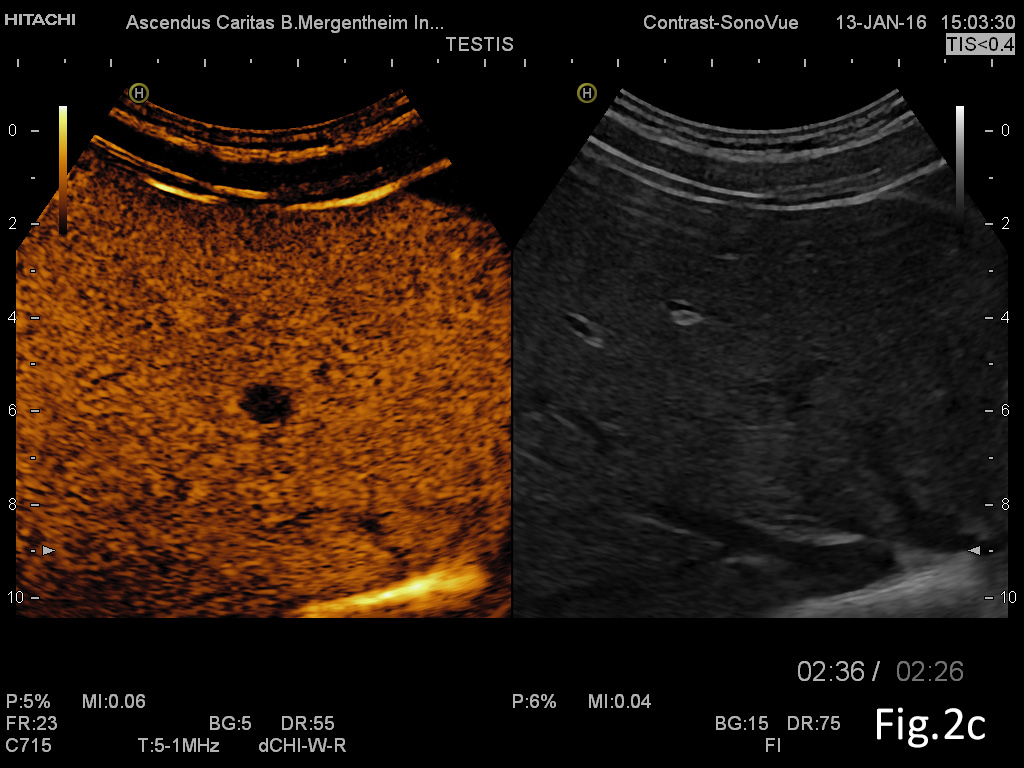

We report on a 28 year old male presenting with unspecific abdominal pain for two weeks. B-mode ultrasound revealed extended abdominal lymphadenopathy [Figure 1] and two small unspectacular hemangioma-like focal liver lesions [Figure 2]. The left testis revealed a palpable tumour by ultrasound also examined with elastography and contrast enhanced ultrasound [Figure 3 and 4]. Endoscopy of the upper gastrointestinal tract showed candida of the esophagus. The biopsy of the abdominal (retroperitoneal) lymph nodes revealed epithelial cells, typical for testicular embryonal cell carcinoma.

Figure 2: Focal liver lesion using B-mode (a) and contrast enhanced ultrasound (CEUS) in the arterial (b), late phase (c) and CEUS using time intensity curve analysis (TICA) (d). The B-mode ultrasound showed an isoechoic lesion with transducer distal shadowing, somewhat unspectacular. CEUS showed early and slightly hyperenhancing features in the arterial phase and pronounced wash out in the portal venous and late phases indicating metastases and excluding hemangioma [(1)]. The TICA image on the right side of the screen differentiates the initially hyperenhancing lesion (red line) in comparison to the surrounding liver parenchyma (yellow line). In the portal venous phase the red line crosses downward in comparison to the liver parenchyma (yellow line), indicating metastasis [(2-5)].